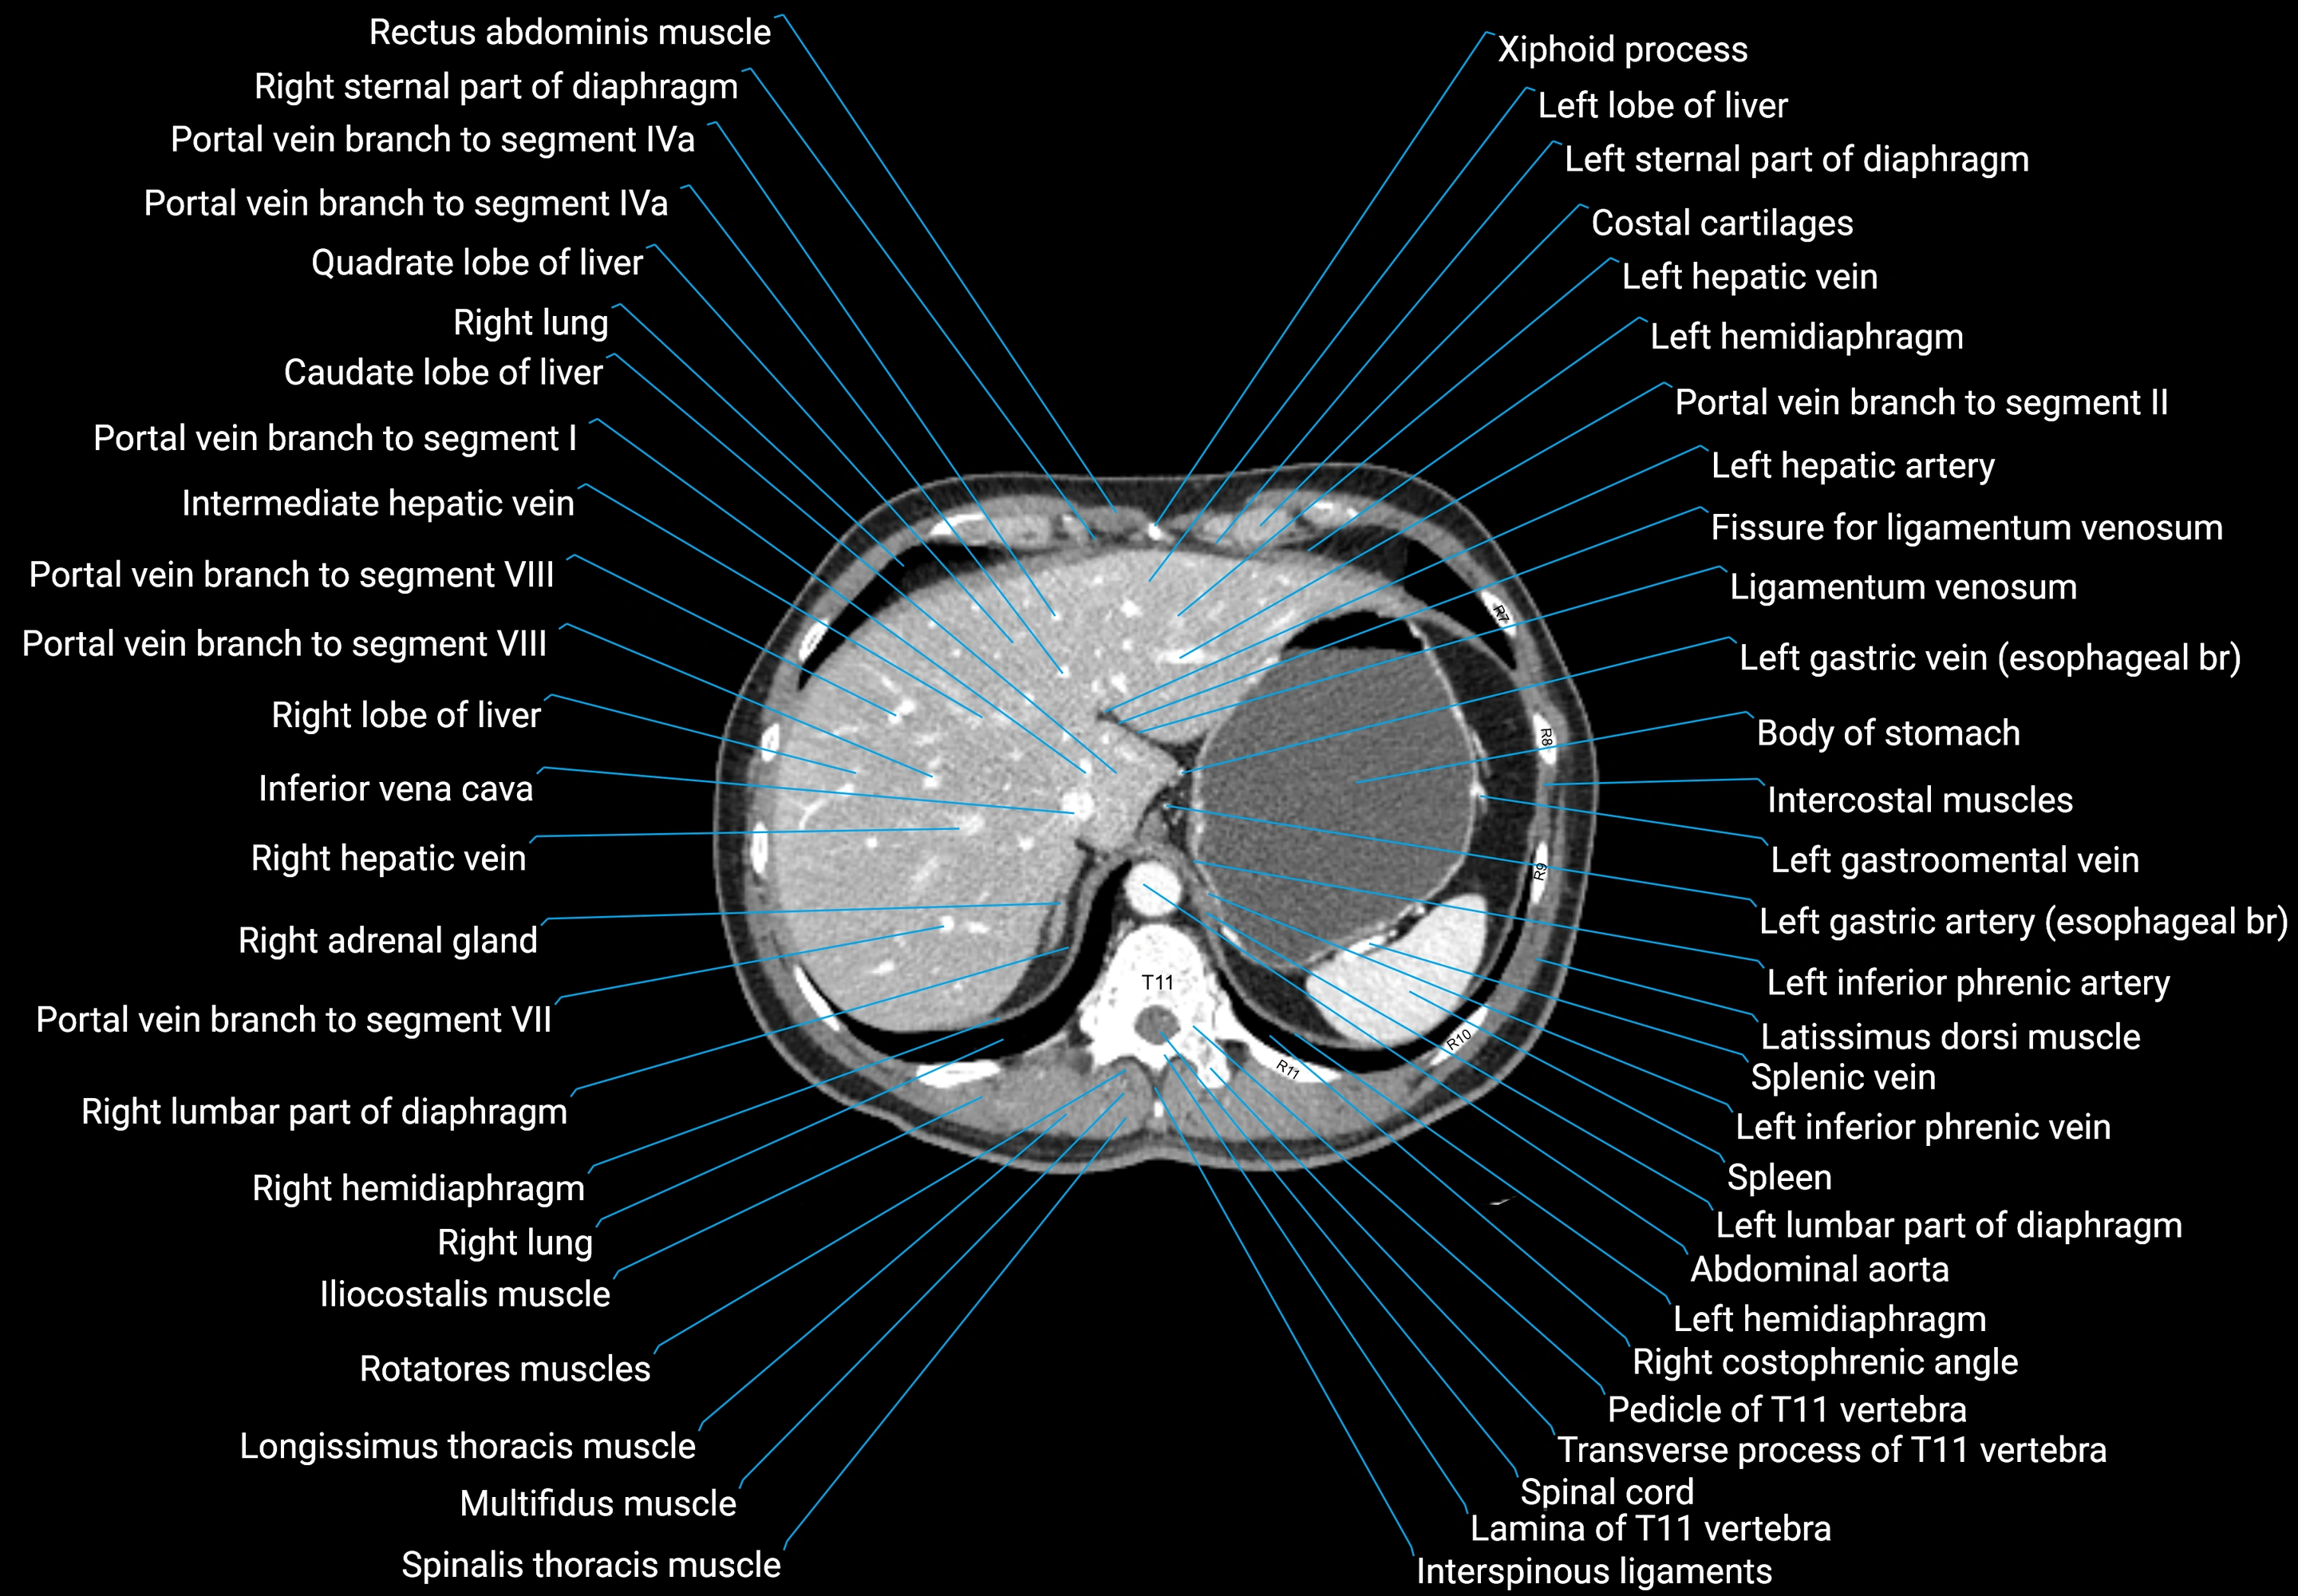

CT images